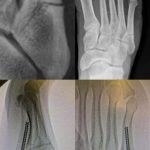

Hediano Sport Club Reportado como jugador Fernon Feron Fue administrado con éxito Quince fracturas metatarsianas en su pie izquierdo. Esto sucedió en el partido contra Gwadalupe el jueves pasado, The Guardian tuvo que cambiar por un tiro fuerte.

Feron compartió fotos en sus redes sociales sobre cómo vivió hace unas horas.